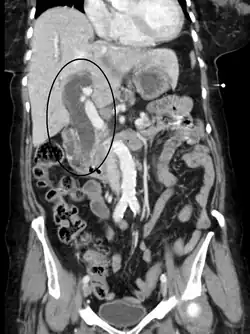

Dilatation des voies biliaires due à une obstruction (scanner, en section horizontale).

Dilatation des voies biliaires due à une obstruction (scanner, en section transversale).